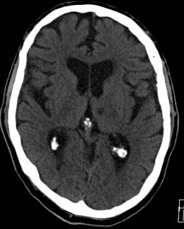

In the hyperacute setting of a stroke what may a brain CT scan show?

May be essentially normal :( but may show hyperdense middle cerebral artery for example